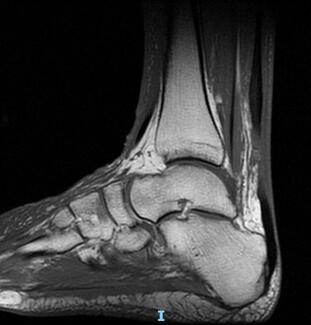

Harry John Visser, DPM, FACFAS; Nicole Marie Smith, DPM

Early identification of, and treatment for, talar avascular necrosis is key to successful outcomes. However, when patients with diagnostic delay present to the office, treatment pathways are not always linear. Here the authors present a...